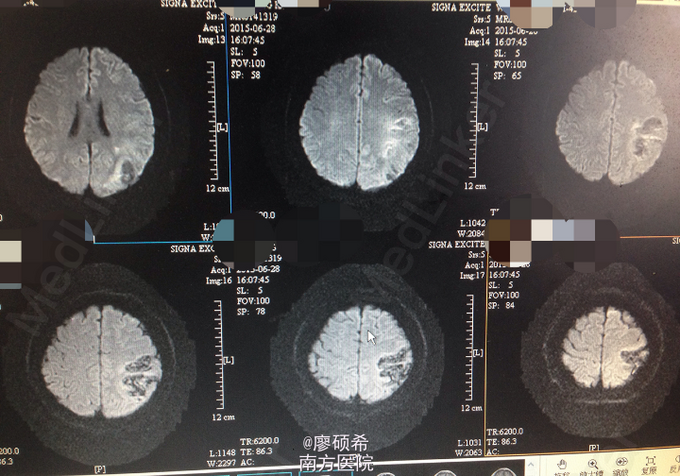

查体:右上肢肌力4级,右下肢及左侧肢体肌力5级;颈稍硬,颏胸距3横指。余查体未见明显异常辅助检查:当地医院急查CT提示左侧颞顶枕叶大片混杂密度信号影,有轻度占位效应。入我院当天予完善腰穿查脑脊液(无色透明)提示压力185mmHg,白细胞计数10个/ul,总蛋白浓度0.5g/L,氯离子124.8mmol/L,葡萄糖5.12mmol/L,ADA0.5U/L。血尿便常规、肝肾功能、电解质心功能均未见明显异常。数日后完善颅脑MR提示:1、左侧顶枕叶皮层及皮层下异常信号,考虑脑梗死并少量出血(非急性期);全组鼻窦及右侧乳突炎症。TCD提示右侧锁骨下动脉可疑狭窄,1期盗血;左侧大脑中动脉可疑狭窄。

初步诊断考虑颅内占位查因:脑脓肿?完善细菌(含结核菌)、真菌病毒等检查均提示阴性。予改善循环、护脑、抗感染等治疗后患者好转出院。经过讨论,结合MR结果,最终考虑脑梗死可能性大,但影像学表现独特。